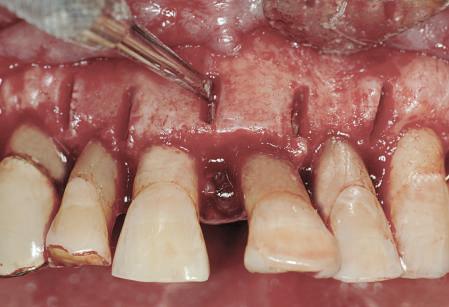

Dacă însă implanturile sunt plasate prea vestibular sau prea superficial, componentele nu permit un design adecvat al bontului, pentru că plasarea marginii este limitată iar conturul facial şi proximal poate fi compromis (fig. 1, 2).

Figurile 3, 4. Întrucât poziţia implantului era mezială faţă de ideal, bonturile individualizate s-au conceput plate pe profilul mezial, dar au prezentat provocări în privinţa conturării restauratoare. 5. Restaurările implantare de la nivelul 1.2. şi 2.2. susţin o FPD metalo-ceramică cimentată între incisivii laterali.

Figurile 1, 2. Compromisurile conturului vestibular şi proximal sunt evidente. Implantul este la nivel tisular, tehnicianul neputând gestiona plasarea marginii sau a profilului intrasulcular pentru a îmbunătăţi estetica. Dacă se concepea un design tradiţional cu hexagon extern, marginea restauratoare s-ar fi putut plasa foarte aproape de interfaţa bont-implant, cu gestionarea mai bună a spaţiului.